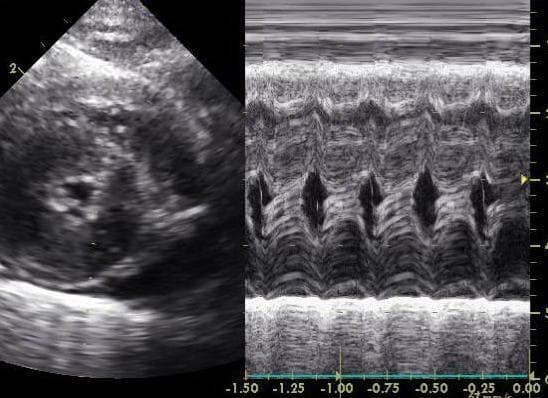

Во время ЭХОКГ оценивают толщину межжелудочковой перегородки или задней стенки левого желудочка. Гипертрофия может быть симметричной – утолщены межжелудочковая перегородка (более 6 мм) и задняя стенка левого желудочка, либо асимметричной – утолщена межжелудочковая перегородка, или задняя стенка левого желудочка, увеличение в размере левого предсердия – более 1,6 мм, и нарушение расслабления левого желудочка.